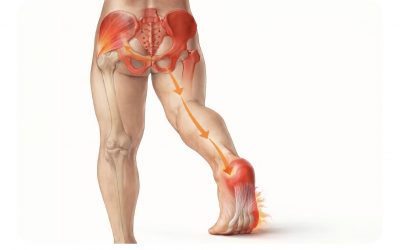

La cadera: origen oculto del dolor de talón.

El efecto dominó del movimiento Muchos pacientes llegan a consulta convencidos de que su dolor de talón es “una fascitis plantar” y sólo en ese punto tiene un problema. Problema que llevan años padeciendo a pesar de haber hecho muchos tratamientos. Tras años de ver y...